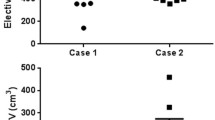

DSC, MSD, HD95 and volumes

Table 1 shows the median DSC, MSD and HD95 per OAR and range for all OARs, for all 5 patients. Median DSC ranges from 0.38 (left cochlea) to 0.90 (mandible), median MSD ranges from 1.1 mm (mandible) to 4.6 mm (oral cavity) and median HD95 from 3.1 mm (submandibular glands) (SMGs) to 14.5 mm (oral cavity). Figure 1 shows the overall difference in MSD between RO who use the ICG versus other RO and Fig. 2 shows the differences per OAR. They show that MSD is significantly smaller when the ICG are applied (p = 0.008). In Additional file 3: Fig. 1, DSC and corresponding MSD for each OAR are shown separately to show that some OARs show more IOV than others. Additional file 4: Fig. 2 shows the difference between the two RO groups for DSC and HD95. Additional file 5: Fig. 3 shows the range of volumes delineated per patient and per OAR compared to OARref.

Nelms et al. [25] showed the impact of OAR contouring variation on dose volume histograms (DVH) and concluded that differences in maximum dose (Dmax) and mean dose (Dmean) per OAR could be large, depending on the degree of IOV and the RT plan. On the one hand there are OARs where Dmax can be used for plan optimisation (mandible, brainstem, spinal cord and cochleas) and for these OARs, precision of the contour (especially in cranial and caudal direction) may be less important because volume does not affect Dmax significantly. Exceptions of course are sub-optimal delineations, for example when OARs (such as cochleas in 2 patients in this study) are delineated in the wrong position. Additionally, the caudal border of the spinal cord is important for caudally located tumours and the cranial border of the spinal cord should also be delineated carefully, as the spinal cord has a stricter dose constraint than the brainstem. Shifting the border between these two OARs more caudally means the spinal cord could receive a higher dose than anticipated. On the other hand, there are OARs (salivary glands, oral cavity, PCMs, glottic area and supraglottic larynx) where Dmean is used for treatment planning and evaluation. In that case, the volume delineated is important because a smaller volume would result in a higher Dmean than a larger volume. Additional file 4: Fig. 2 shows that for the glottic area, oral cavity and supraglottic larynx, the smallest/largest volume contoured by RO is sometimes half/double the size of the OARref volume. A summary of the impact of sub-optimal delineations on dosimetry is listed in Table 2.

The boxplots depict the variation in volumes delineated by the different radiation oncologists for each patient separately. The boxplot shows the interquartile range (IQR), the median (horizontal line) and the minimum and maximum volume delineated (whiskers). OARref shows the organ at risk volume delineated according to the international consensus guidelines of Brouwer et al.